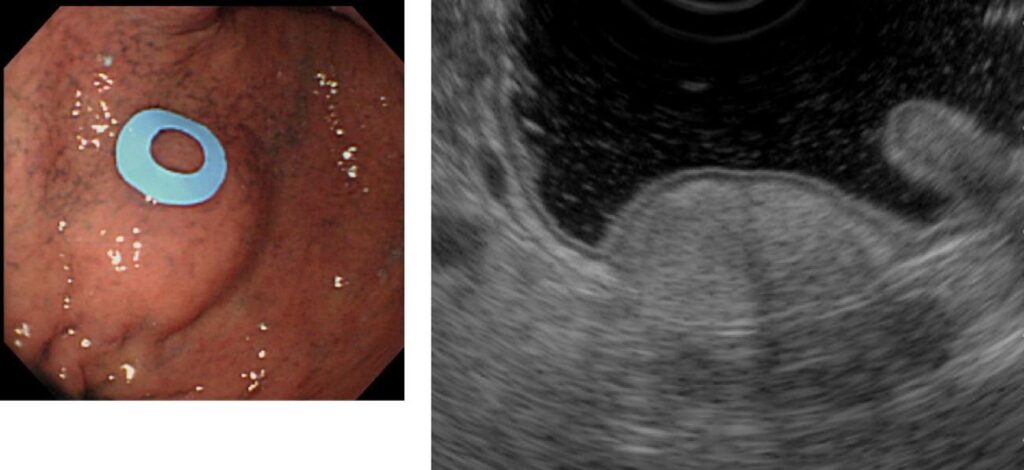

左が胃内視鏡、右がEUS

超音波内視鏡検査(EUS)

EUSとは、胃カメラに超音波を出す装置がついたもので、組織の構造が変化する部位で音波が跳ね返ってくる現象(エコー)を利用して、跳ね返りの強さや部位を画像として映し出すことで、粘膜の下の構造、腫瘍を詳しく調べることができます。通常の胃カメラの検査よりも時間がかかるため、鎮静剤を使用して眠っている間に検査を行うことがほとんどです。

粘膜の下に存在する腫瘍の特徴を観察することで、より正確な診断が可能になります。